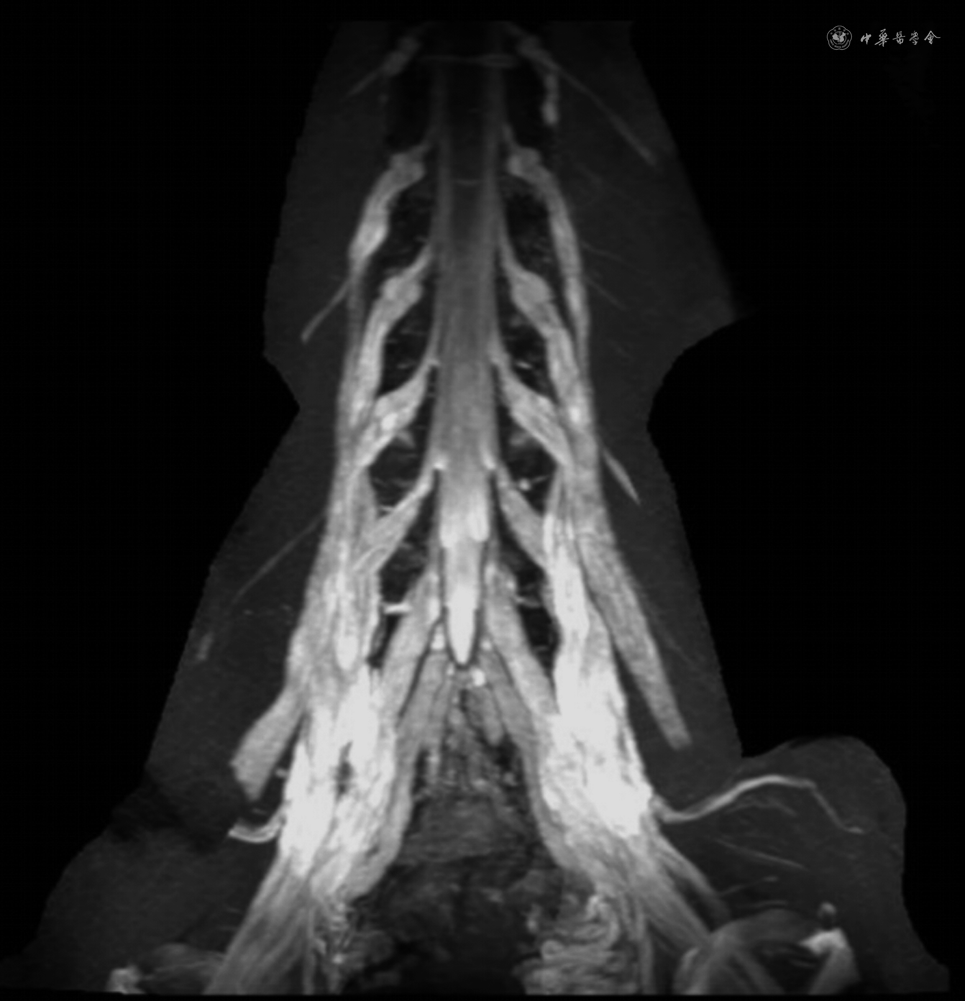

超声检查有助于遗传性和免疫性神经病的鉴别[23],可以在电生理检查正常的患者中发现莰压神经病,慢性炎性脱髓鞘性多发性神经病的周围神经非均匀增粗不同于遗传性运动感觉神经病1型的均匀性增粗,而轴索性神经病患者出现非均匀性神经增粗是血管炎神经病的特征[24]。MRI检查显示神经根出现增粗、水肿或强化见于慢性炎性脱髓鞘性多发性神经病以及郎飞结病(图3),而神经干局部变细是沙漏样狭窄神经病的特点[6]。